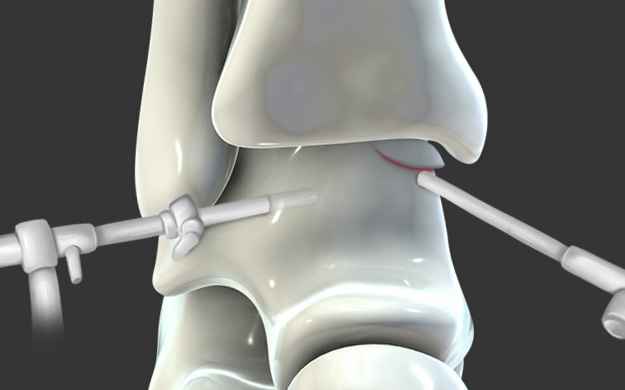

관절경을 통하여 손상된 연골 부위를 정리하고 뼈에 작은 구멍을

여러 개 뚫어서 연골 재생을 유도하는 방법입니다.

섬유성 연골로 재생되나 미세 천공술 단독으로도

특히 발목에는 효과가 좋습니다.

연골 손상이 있는 부위에 작은 구멍을 여러 개 내준 후, 골수에서부터 좋은 피가 잘 올라오는 것을 확인합니다.

연골 재생술을 같이 하는 것이 계획되었다면 콜라겐 혹은 줄기 세포로 결손부위를 도포해줍니다.